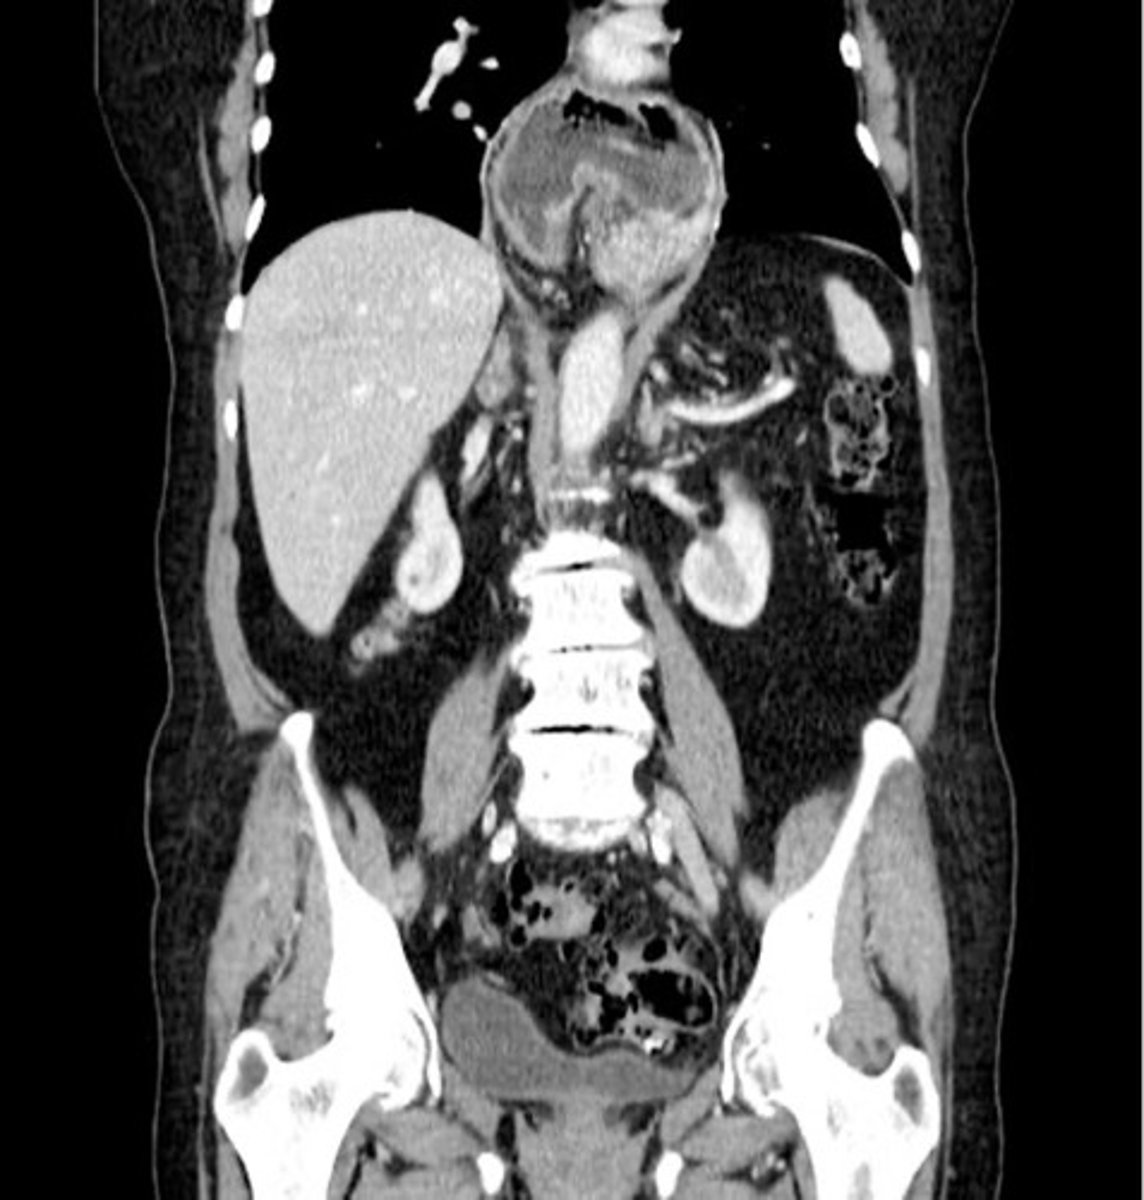

Paraesophageal hernia CT

stomach is in chest

Paraesophageal hernia CT (pic 2)